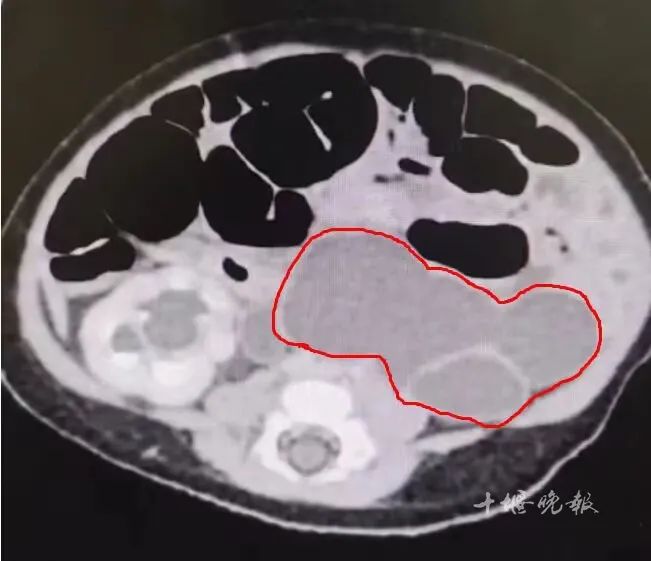

输尿管严重扩张,占据婴儿大部分体腔。

李云飞为当时刚满40天的辰辰完善相关检查,发现辰辰为左侧输尿管全程重度畸形扭曲导致梗阻,部分严重扩张。原本正常情况下仅有2-3毫米直径粗细的输尿管已扩张至近50毫米,占据大部分盆腔位置,并压迫周围组织结构。其上腹部有明显可触包块,如不紧急治疗,可能造成肾脏不可逆性损害,严重时导致肾切除。